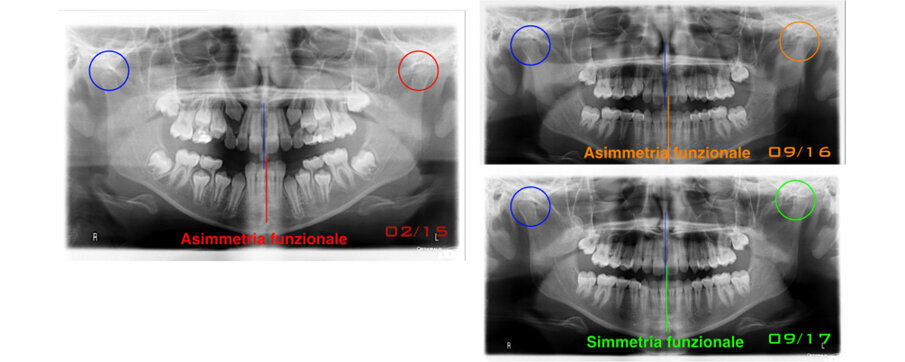

Caso 1 Paziente di anni 9,5, II Classe scheletrica, retrusione mandibolare, contrazione dell’arcata superiore, Overjet elevato (9,5 mm), compressione delle vertebre cervicali. La paziente riferisce di soffrire di cefalee continue. Dall’esame della panoramica e della teleradiografia evince una grande discrepanza tra il condilo dx e sx ed un evidente riduzione dello spazio intervertebrale in corrispondenza delle prime vertebre cervicali. La paziente è sottoposta a terapia elastodontica con AMCOP di seconda classe SC 3 con lo scopo di favorire l’espansione dell’arcata superiore e l’avanzamento mandibolare. A distanza di un anno evince un miglioramento dell’articolazione temporo-mandibolare di sx ed un aumento dello spazio intervertebrale legato a l’avanzamento mandibolare, è evidente inoltre il miglioramento dell’overbite ed overjet. A distanza di 2 anni si assiste ad un netto miglioramento dei condili grazie all’azione scheletrica dell’AMCOP ed a un netto vantaggio posturale con aumento dello spazio tra le vertebre cervicali. La malocclusione si può dire risolta anche se necessita una stabilizzazione del caso clinico attraverso lo stesso dispositivo (Figg. 2-14).

Fig. 2

Fig. 3

Fig. 4

Fig. 5

Fig. 6

Fig. 7

Fig. 8

Fig. 9

Fig. 10

Fig. 11

Fig. 12

Fig. 13

Fig. 14

Il caso clinico dimostra come la malocclusione scheletrica avesse delle forti ripercussioni sulla postura e come risolvendo la malocclusione scheletrica si ha anche un ottimo equilibrio posturale come evince dalle teleradiografie.